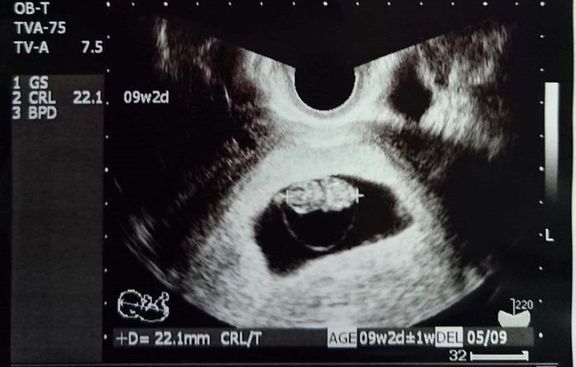

"おなかの中はどうなっていくの? エコー写真で振り返る、高齢ママのはじめての妊娠生活" -

「5回目の体外受精で妊娠」エコー写真で綴る “高齢妊婦が赤ちゃんに出会うまで“の泣き笑い日記 -

緊急帝王切開で誕生。エコー写真で綴る息子と過ごした252日 -

不妊治療や2度の流産経験を経て「初めての出産」。日々成長する胎児の記録をエコー画像で振り返る -

待望の妊娠判明!エコー写真に見る、我が子を胸に抱くまでの“命の軌跡275日” -